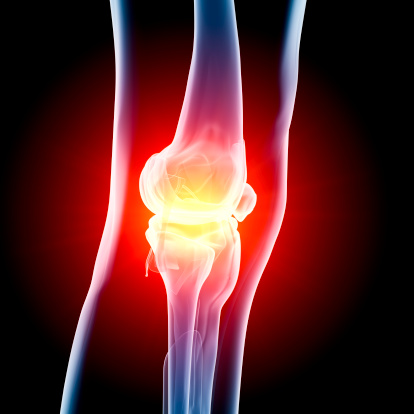

Fact Or Myth? Cracking Knuckles Causes Arthritis

You’ve most likely heard the phrase, “Don’t crack your knuckles or you’ll get arthritis.” This may have stopped you for the time being, but once no one was around, you probably went right back at it. (It feels so good!) But does the saying hold any truth? Or is it just an old wive’s tale? ...click here to read more